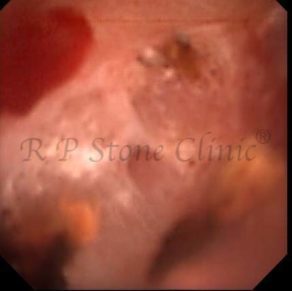

Kidney stone is a solid mass of CRYSTALS. It is the process of crystallization which initiates the formation of kidney stones. This happens in nephrons or units of kidney. Once a small crystal is formed, it can both grow & unite with other crystals leading to the formation of small concretion which eventually forms a stone. Once these large crystals detach from the collecting ducts, the process of stone formation starts in the renal collecting system. A recurrent kidney stone former is advised to know a little bit about something known as Randall’s plaque. Alexander Randall discovered plaques on the renal papillae eight decades back based on examination of 1154 pairs of autopsied Kidneys. He described these renal papillary lesions as cream colored or milk patch areas composed of calcium phosphate & calcium carbonate. These plaques could act as NIDUS for formation of KIDNEY STONE. Calcium Oxalate stone can form on this nidus & then detaches from this plaque to become a free floating stone in the collecting system of kidney

These images are taken as snap shots from the video recording of RIRS Surgery done at our hospital. These are Randall’s Plaques seen with Digital FLEX XC & Digital FLEX XC S. The cream or whitish patches are seen on the tips of RENAL PAPILLAE as seen in images below.